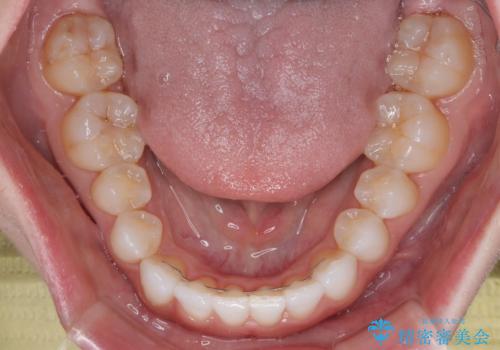

- 上下前歯の叢生を気にして来院された患者様です。

インビザラインでの治療を希望されていて、デコボコの程度が中等度であり、安価なパッケージにて対応可能と判断されたため、インビザライン・モデレートを用いて矯正治療を行うこととしました。